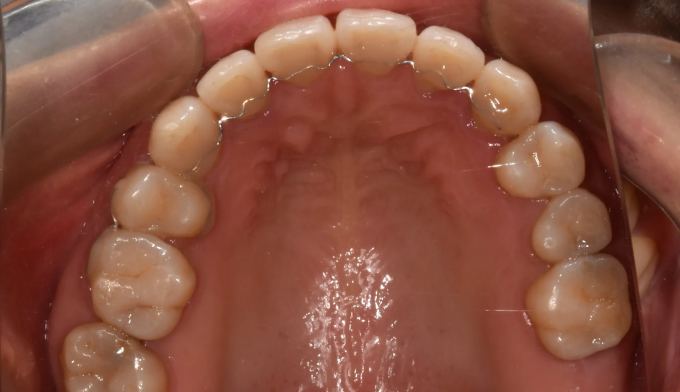

어금니가 상실된 경우, 보통 해당공간에 임플란트를 식립합니다. 하지만 보철치료에 대한 거부감이 있거나, 그 폭이 애매하게 좁은 경우, 교정치료를 통해 공간을 닫는것이 효과적인 경우가 많습니다.

해당 케이스에서는 반대쪽 어금니도 없었기 때문에 짝을 맞추기 위하여 임플란트 식립 대신 해당 공간을 교정치료를 통해 닫기로 하였습니다.

9개월만에 2개의 어금니를 전방으로 이동시켜 아래 어금니와 안정적인 교합을 형성하였습니다. 임플란트 없이 본인의 치아로 불편함없이 지낼 수 있게 되었습니다.